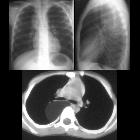

School ager

with cough and fever. CXR PA and lateral (above) shows a right sided chest mass in the posterior mediastinum. Axial CT with contrast of the chest (below) shows a homogeneous mass, of fat density, with a few septations, in the right posterior mediastinum causing some anterior displacement of the right mainstem bronchus.The diagnosis was lipoblastoma in the posterior mediastinum.